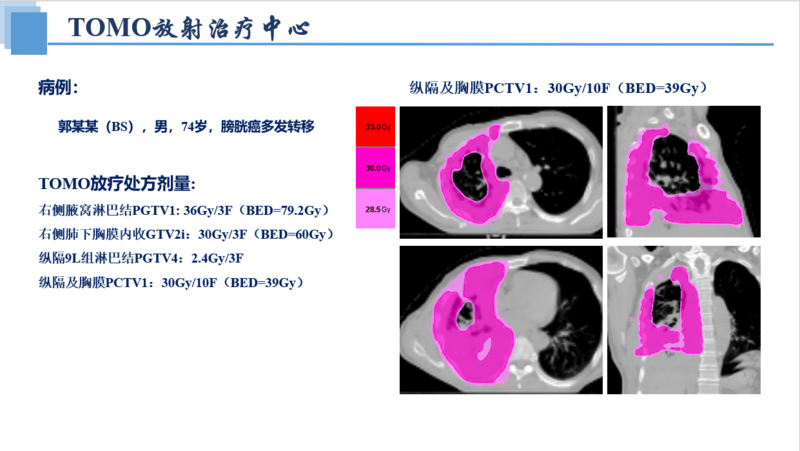

1例(男/74岁)膀胱癌多发转移(肺、骨、肝、脾、胸膜、纵隔、腹膜后、皮肤等)-TOMO放疗

郭某某(BS),男,74岁(出生时间:1949-02-01)

放疗处方剂量: